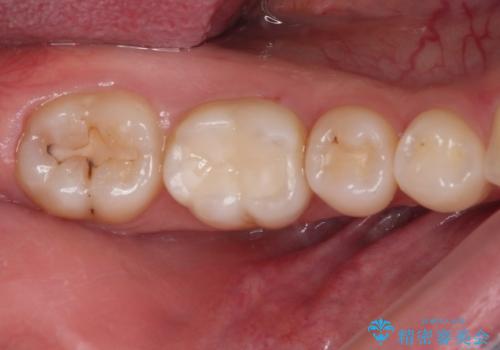

見た目、噛み合わせともに満足していただけました。

ラバーダム防湿を行い、セラミックの接着をすることで、唾液や血液などの接着阻害因子を排除することができます。